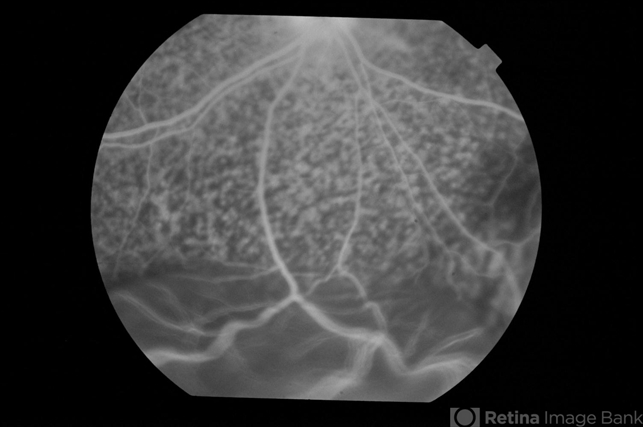

- uveitis, exudative retinal detachment

- Fluorescein angiogram of an elderly patient with bilateral posterior uveitis shows punctate hyperfluorescence and inferior RD. He responded well to oral steroids with complete resolution of the uveitis and RD.